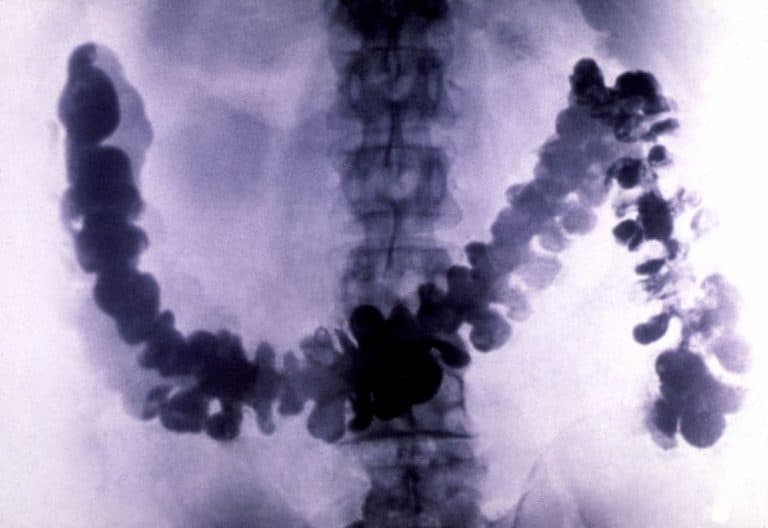

ويُعد تنظير القولون إجراءً سهلاً نسبياً، ويمكن بوساطته اكتشاف سرطان القولون والمستقيم في مرحلة مبكرة، عندما لا يزال في مرحلة البوليبات (الزوائد اللحمية)، والتي يمكن استئصالها بسهولة ومنعها من التطور إلى سرطان حقيقي.